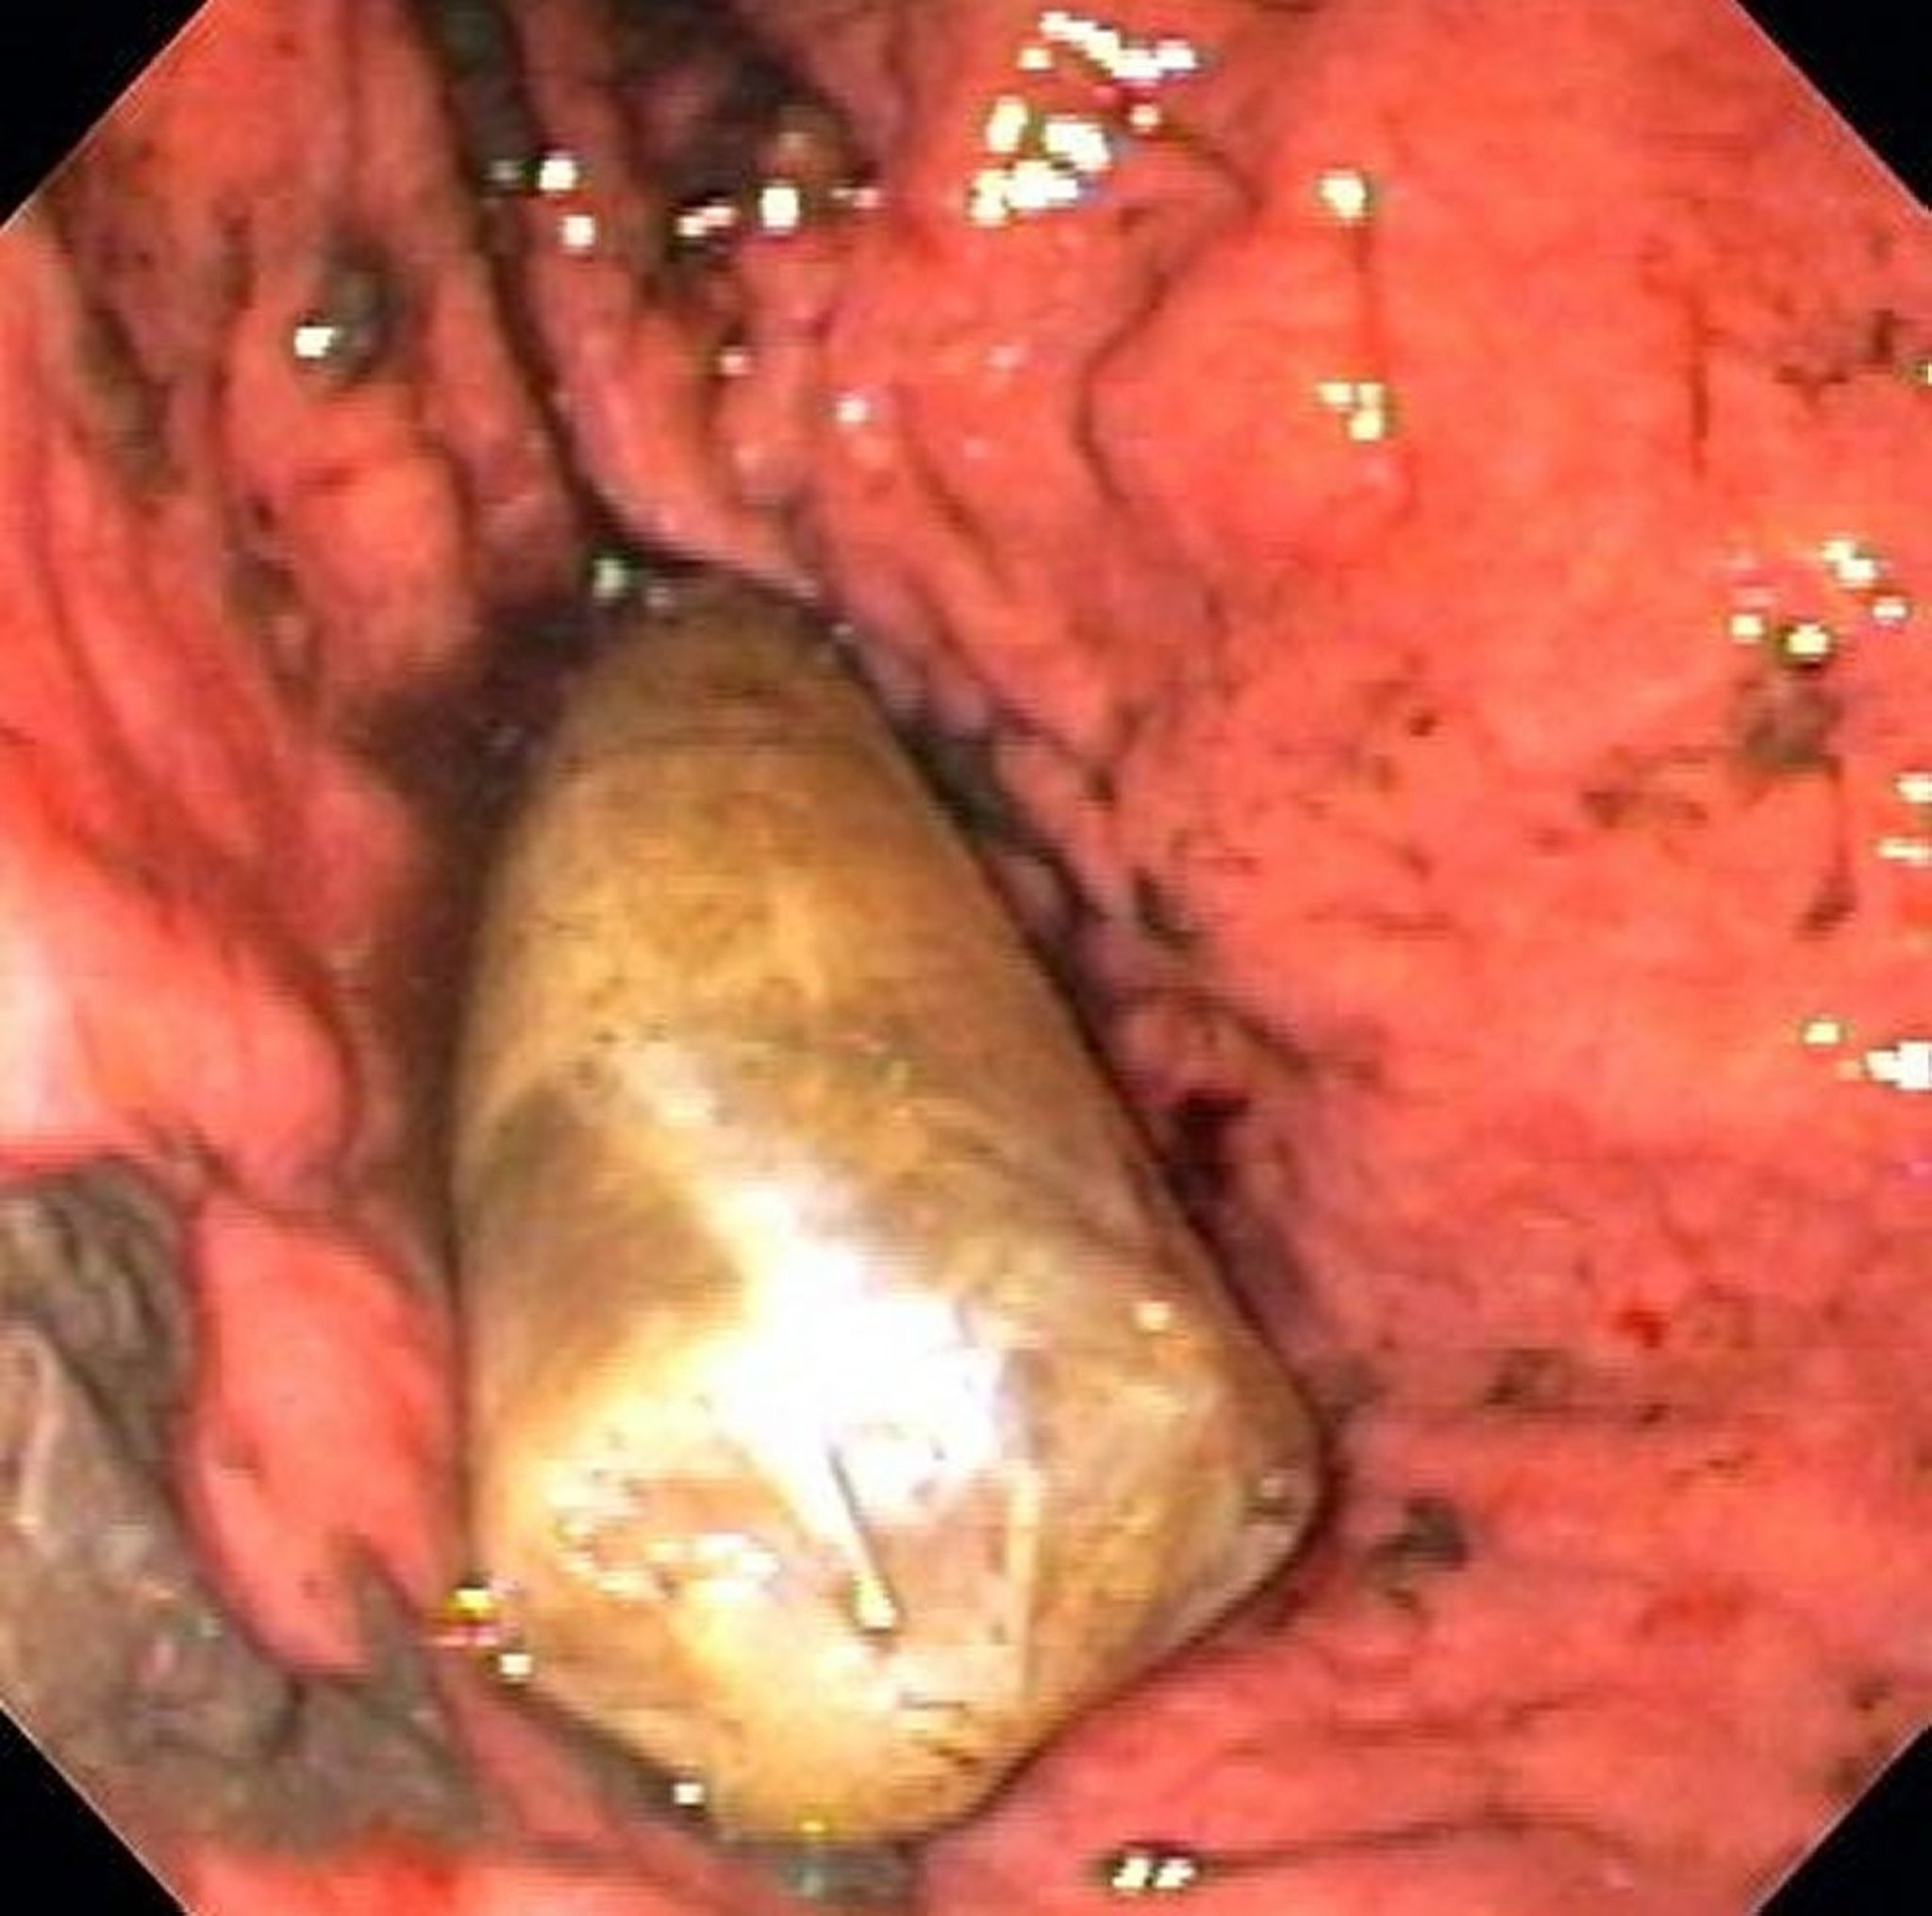

Corps étranger dans l’estomac (endoscopie)

Cette image montre un paquet de drogue dans l’estomac.

Image fournie par Alan Gingold, DO.